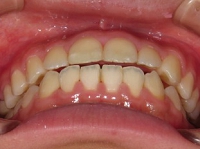

↓歯列(下顎)が左へズレている例(初診時)

。。。。

.⇒.

.:矯正治療中

☆上下のアーチの形をライトワイヤー装置にて

修正すると,下顎のズレが解消されました.